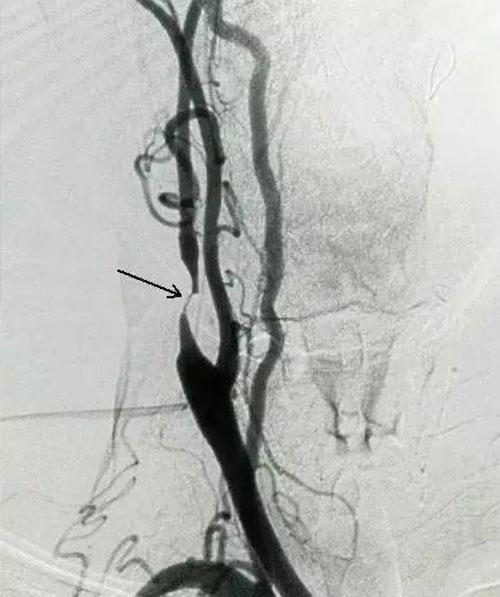

1927年,影像科医生通过血管造影发现:一些脑血管正常的人,颈内动脉却形成斑块,造成狭窄,这证明颈内动脉先于脑血管形成狭窄,颈内动脉狭窄与脑中风是因果关系,颈内动脉狭窄是因,脑血管狭窄是果,颈内动脉狭窄最终会引发脑中风。

1954年,一名医生为一个脑中风病人检查,发现病人脖子一侧的颈内动脉形成了斑块堵塞,于是就为病人实施了颈内动脉斑块剥离手术,结果病人的症状得到了显著缓解。这一案例被广泛报道,引起了全世界关注。但是由于手术的技术难度大,风险也大,所以并未得到推广。

颈动脉狭窄的干预标准是:只要有斑块就要用他汀类药物治疗;颈动脉管腔被挤占50%以上,对大脑的供血就会不足,需要针对斑块的软硬、面积的大小、斑块的多少,选择药物治疗、支架介入、斑块剥离手术;颈动脉管腔被挤占80%以上,随时都可能发生脑中风,急需治疗。